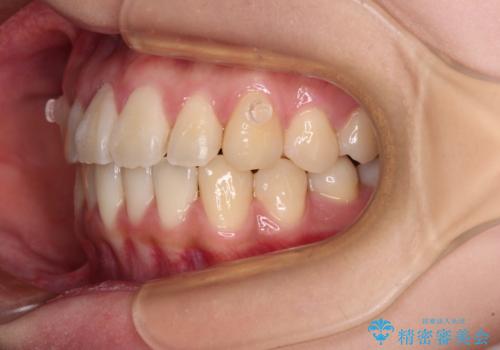

しっかりと装着時間を守ってくださったので、予定通り1年強で治療を終えることができました。